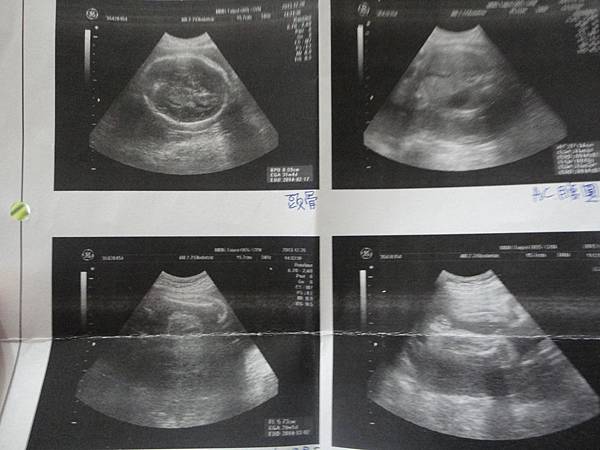

原本的超音波照樂樂大概是1879g

新的估計是1789g(還是很大==)

醫生說頭跟腹部和腿長都有比別的寶寶大1-2w

(分別是頭.腹跟大腿長&體重)